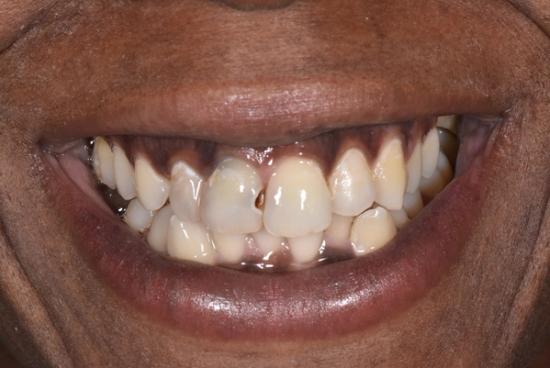

Before Photo